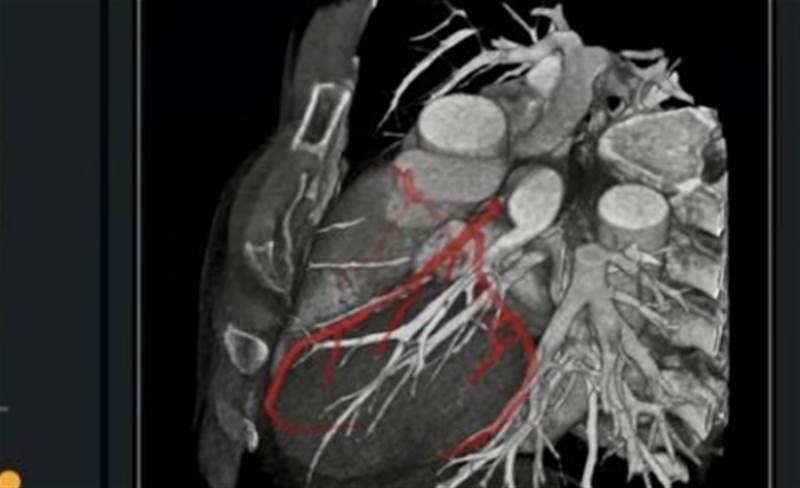

While international guidelines recommend computed tomography coronary angiography (CTCA) as the first-line investigative tool for coronary artery disease (CAD), interpretation of the resultant CT scans is time-consuming, generally requiring one to two hours for standard cases and even up to four hours in complex cases for clinicians.

Synapxe said that the platform utilises AI algorithms and patented post-processing technologies to deliver precise measurements and assessments for coronary calcium scores, epicardial adipose tissue (EAT), stenosis and plaque, which together with the CTCA interpretation, represents a comprehensive CAD evaluation.